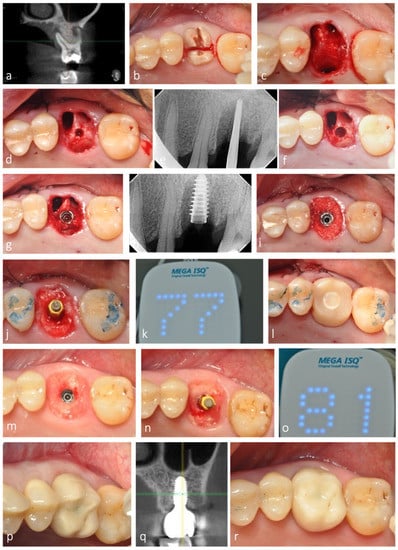

Septum width was directly measured post molar extraction. Measurement was recorded at the narrowest width of the septum. Implant site preparation started with a pilot drill, in clockwise motion, in the center of the septum, until 1 mm deeper than the planned implant length. Densah® Burs (Versah, LLC, Jackson, MI, USA) were then sequentially used in OD mode (counterclockwise, drilling speed 800–1500 rpm, with copious irrigation) in small increments to gradually expand the osteotomy, until reaching the desired width for the planned implant diameter (Figure 1).

Figure 1.

Clinical examples of interradicular septum expansion after implant site preparation with osseodensification ((A). Mandibular first molar; (B). Maxillary second molar).

All sockets evaluated in this retrospective analysis were grafted with either allograft or alloplast (Novabone®). Bone grafting of the remaining socket voids adjacent to an immediate implant is not essential for osseointegration to occur, especially if the outer walls of the socket are intact [,,]. However, its combination with a customized healing abutment, acting as a prosthetic socket seal device minimizes the amount of ridge contour change after tooth extraction and IIP, thereby contributing to better esthetics and restorative contour [,], as observed in this study (Figure 8).

Figure 8.

Representative clinical case with 3-year clinical and radiographic follow-up. (a) CBCT of maxillary left first molar showing periapical infection with extensive bone loss buccally and palatally. (b) Root section for tooth extraction as atraumatic as possible. (c) Septum preservation after extraction. (d,e) Initial osteotomy depth at 10 mm. (f) Implant site preparation, optimized with osseodensification. (g,h) Implant placed in the expanded septum. (i) Allograft placed in the root sockets to fill the extraction socket. (j–l) Adequate implant stability allowed for the placement of a fully contoured customized socket sealing healing abutment out of occlusion. (m) Healing after 3 months, with contour maintenance. (n,o) ISQ measurement after osseointegration period. (p–r) Clinical and radiographic follow-up after 3 years.